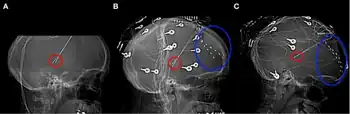

| a-c) Thalamic stimulator contacts in red, subdural electrodes in blue. | |